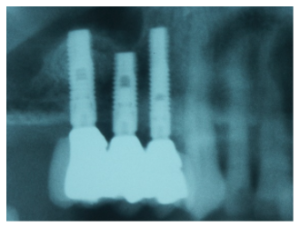

Imagen de la rx con los implantes colocados, e imagen de la prótesis acrílica.

Foto de la rx tras la colocación de los implantes máxilo-mandibulares